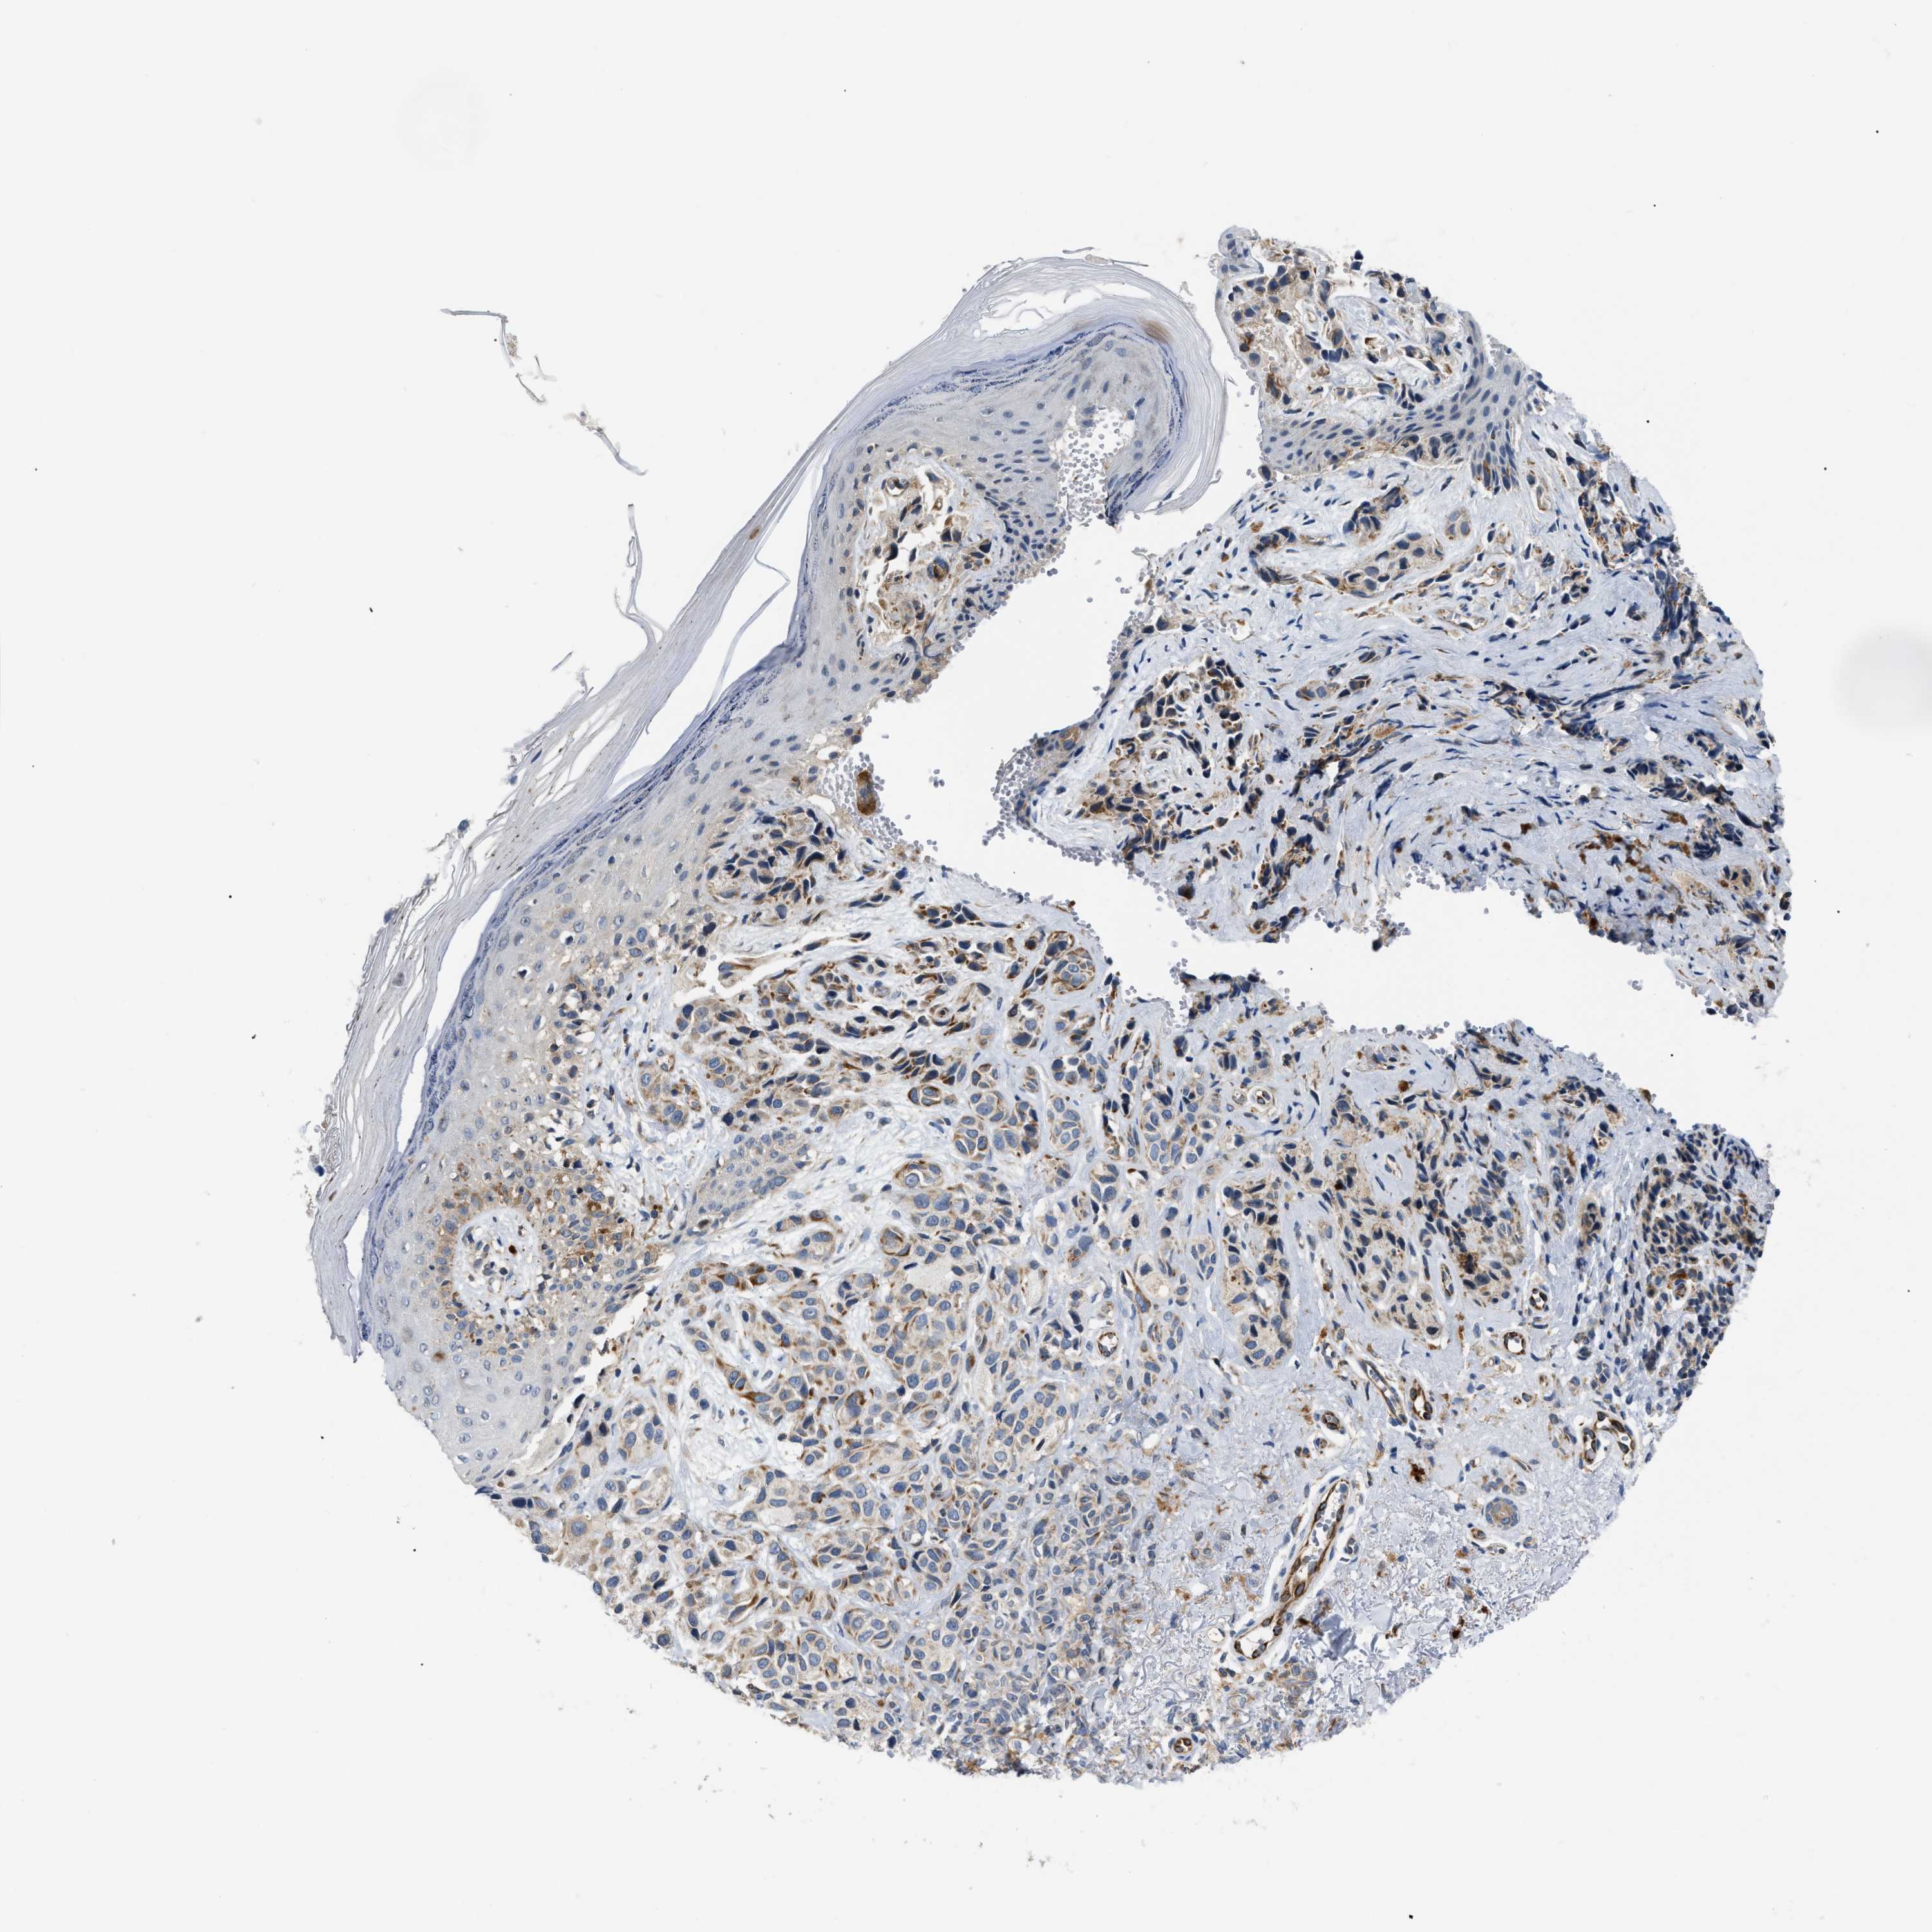

MELANOMA - Protein expressioni

A mouse-over function shows sample information and annotation data. Click on an image to view it in a full screen mode. Samples can be filtered based on level of antibody staining by selecting one or several of the following categories: high, medium, low and not detected. The assay and annotation is described here.

Note that samples used for immunohistochemistry by the Human Protein Atlas do not correspond to samples in the TCGA dataset.

Antibody stainingi

Antibody staining in the annotated cell types in the current human tissue is reported as not detected, low, medium, or high, based on conventional immunohistochemistry profiling in selected tissues. This score is based on the combination of the staining intensity and fraction of stained cells.

Each image is clickable and will lead to virtual microscopy that enables deeper exploration of all samples and also displays staining intensity scores, fraction scores and subcellular localization as well as patient and tissue information for each sample.

Antibody HPA018670

Antibody HPA019570

Staining

High

Medium

Low

Not detected

Intensity

Strong

Moderate

Weak

Negative

Quantity

>75%

75%-25%

<25%

None

Location

Nuclear

Cytoplasmic/membranous

Cytoplasmic/membranous,nuclear

Malignant melanoma, NOS

Malignant melanoma, Metastatic site